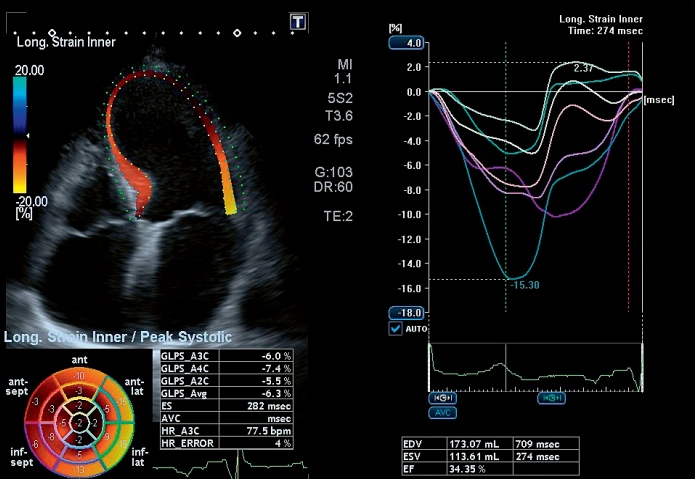

Кардио-пакет

- ЭКГ,

- Трекинг смещения стенки миокарда,

- Стресс эхо-кардиография,

- Определение индекса васкуляризации.

Полный пакет стресс-эхо для быстрой и точной оценки движения стенок миокарда.

Технология трекинга миокарда позволяет оперативно проводить качественную и количественную оценку глобальной и региональной сократимости миокарда.